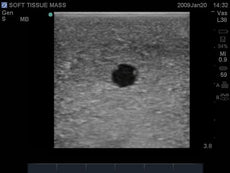

This CAE Blue Phantom foreign body single leg model is ideal for learning image acquisition and interpretation, and practicing the psychomotor skills necessary for ultrasound diagnosis, and ultrasound-guided procedures. Our patented Simulex tissue inserts allow learners to learn ultrasound system controls, positioning and moving the transducer and recognizing anatomy.

Foreign Bodies:- Metal projectile BBs

- Metal shrapnel fragments

- Wooden splinters

- Metal needles

- Large glass fragments

- Glass shards